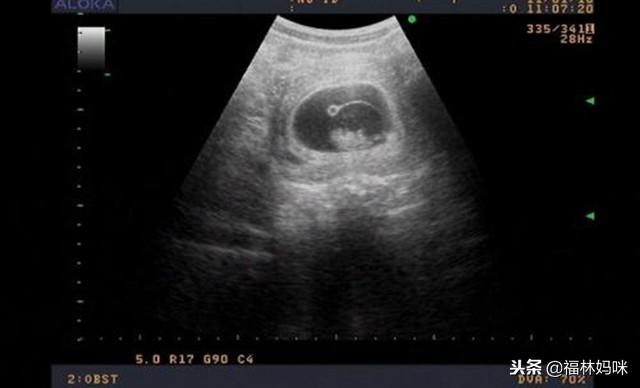

孕酮的正常值是在25ng/ml , 孕酮过低 , 子宫肌会过度活跃 , 这样的话 , 还没有形成胎盘的胚胎可能会被孕妈的身体排出体外 , 造成流产 。 生活中常出现的孕早期见红 , 就是因为孕酮值较低 , 有流产的风险 。